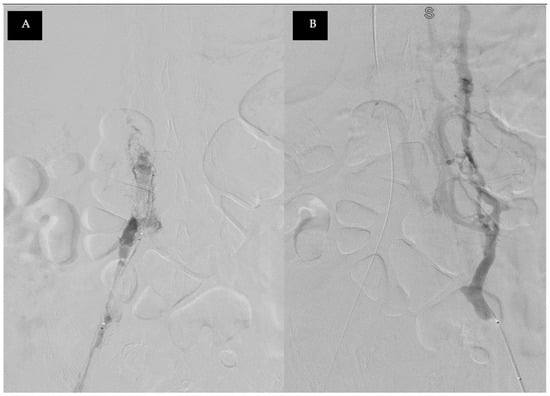

2. Detailed Case Description